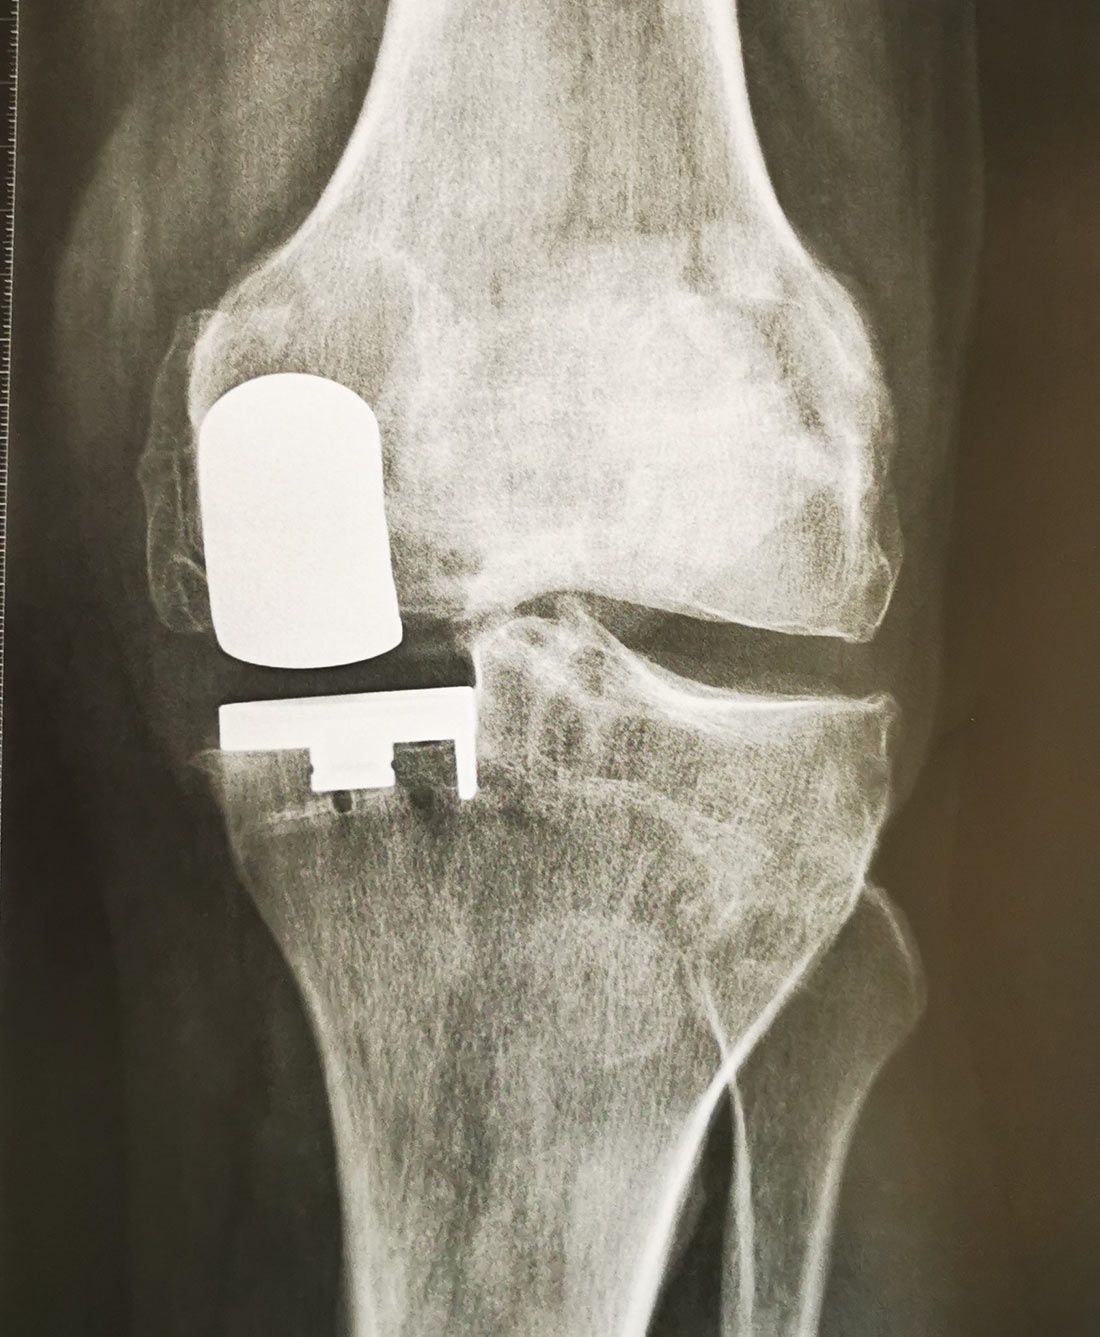

Les Prothèses Unicompartimentales du Genou (PUC)

Lorsque l’arthrose ne touche pas l’intégralité du genou mais seulement un des 3 compartiments, on peut parfois proposer une prothèse unicompartimentale. Ainsi, il existe des prothèses unicompartimentales médiales, latérales ou fémoro-patellaires.

Comme pour une prothèse totale du genou, une PUC nécessite un genou qui devient résistant à un traitement médical bien conduit. On considérera toutefois que les PUC sont de bonnes alternatives à d’autres traitements tels que l’ostéotomie chez des patients de plus de 50 ans.

Les résultats des PUC sont bien souvent excellents avec un genou presque totalement indolore et une prothèse bien souvent « oubliée ».